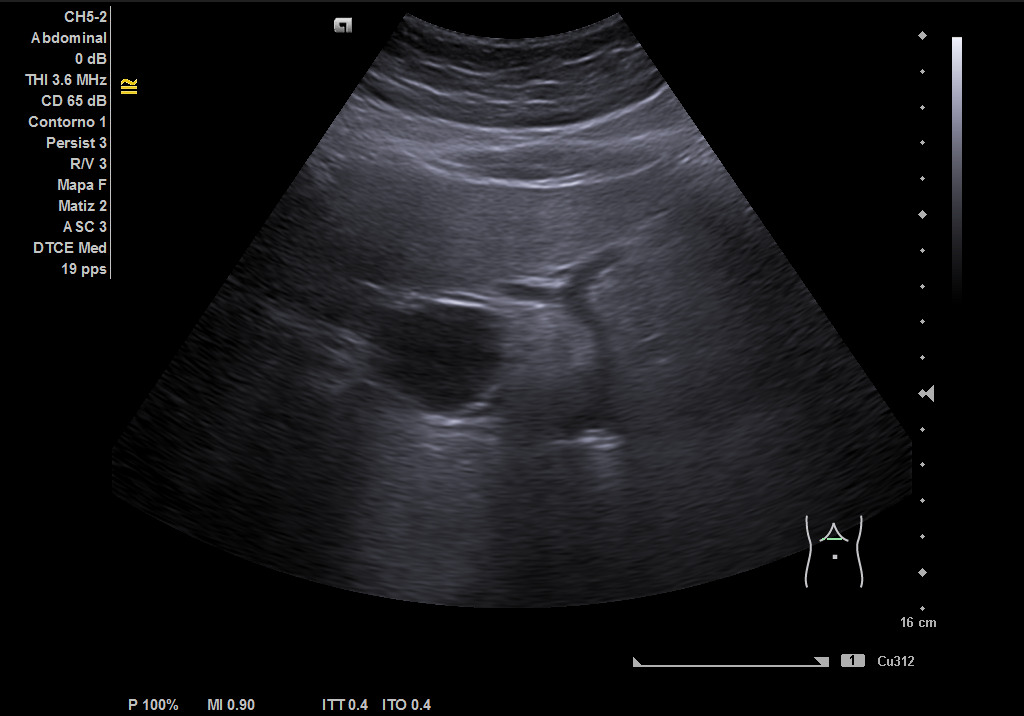

Ecografía clínica: hígado de tamaño y contornos conservados, con aumento difuso de la ecogenicidad, sin presencia de lesiones focales en las porciones visualizadas. Vesícula biliar alitiásica de tamaño y paredes normales. Vía biliar no dilatada. Imagen redondeada de 36,5 mm hipoecoica homogénea que muestra flujo con el Doppler que corresponde con porta extrahepática. Páncreas parcialmente visualizado sin alteraciones valorables. Bazo de tamaño conservado. Ambos riñones normoposicionados, de tamaño y grosor cortical conservados con buena diferenciación corticosinusal. Vejiga replecionada de paredes lisas. No líquido libre intrabdominal. Imagen redondeada de 36,5 mm hipoecoica homogénea que muestra flujo con el Doppler que corresponde con porta extrahepática. Conclusión: esteatosis hepática grado II, imagen redondeada de 36.5mm hipoecoica homogénea que muestra flujo con el Doppler que corresponde con porta extrahepática.

Ecografía: esteatosis hepática moderada e imagen altamente sugestiva de aneurisma de la vena porta extrahepática, permeable y de unos 39 mm aproximadamente.

Aneurisma de vena porta extrahepática.